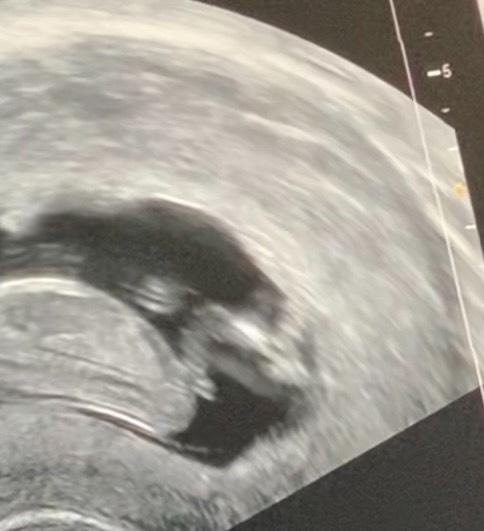

Hi Zusammen, war heute ebenfalls beim Arzt und es sieht alles tiptop aus! Durfte für meinen Mann auch ein kleines Video machen, beim erneuten anschauen glauben wir hier könnte man vielleicht schon ein Geschlecht deuten? Oder was könnte das sein? :-) Schöne Weihnachten euch!

Bild zu Geschlechterraten - was meint ihr? - Forum für Juli - Mamis

Also laut Nub Theorie würde ich ja Mädchen sagen, aber ist auch noch etwas früh. Schön, dass alles bestens ist. LG

Da würde ich mich anschließen und auch klar Mädchen sagen, wenn man nach der Nub Theorie geht. Liegt ja auch alles vertikal, bei uns stand es hoch und wir kriegen diesmal einen Jungen. Glückwünsch, dass alles gut ist.... Dann jetzt die Festtage genießen